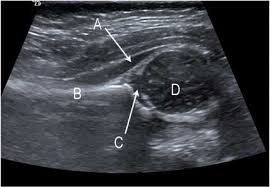

When evaluating a patient with a thyroid nodule, assessment of the lymph nodes, particularly in the lateral neck, provides important clues regarding the malignancy risk. In addition, the following tests may be used to diagnose head and neck cancer: Optimal positioning and exposure of the neck for ultrasound of the thyroid and parathyroid glands (a, b) and lateral neck for lymph node examination and mapping (c).while the vast majority of patients are supine on the exam table with a pillow supporting the shoulders to allow gentle neck extension, keep in mind that some patients have beautiful anatomy (d) that allows ultrasound exam even in. A biopsy can be performed in cases where ultrasound cannot differentiate benign from malignant tumours. Before the node starts the lesions even very experienced specialist, the device will be able to register an increase, its contour irregularity, violation of the structure.

Physical examination/blood and urine tests. Surgical levels of the neck. Ultrasound and mapping of neck lymph nodes. Ultrasound is often one of the first line tests in the detection of cancer. Ultrasound does not show the structures inside joints, dr. Doctors often use ultrasound to guide a needle to do a biopsy (taking out fluid or small pieces of tissue to be looked at under a microscope). It can be used with a fine needle aspiration test or core biopsy test to accurately direct the tip of the needle into the lump. Before the node starts the lesions even very experienced specialist, the device will be able to register an increase, its contour irregularity, violation of the structure. The ultrasound technician (sonographer) may position your head to better access the side of your neck. Likewise, how do they test for thyroid cancer? A biopsy can be performed in cases where ultrasound cannot differentiate benign from malignant tumours. Keep in mind, however, that an ultrasound alone cannot make the diagnosis of cancer. Fna might also be used in patients whose cancer has been treated by surgery and/or radiation therapy, to help find out if a neck mass in the treated area is scar tissue or if it's a return (recurrence) of the cancer.

Ultrasoundis very sensitive and showsmany nodules that cannot be felt. In addition, the following tests may be used to diagnose head and neck cancer: Ultrasound does not show the structures inside joints, dr. Fna might also be used in patients whose cancer has been treated by surgery and/or radiation therapy, to help find out if a neck mass in the treated area is scar tissue or if it's a return (recurrence) of the cancer. Ultrasound technology cannot find ulcers, but other types of diagnostic tests can. Some research explores the potential for finding ulcers with an ultrasound, but experts do not have enough data to recommend it. The path report states loose fragments of poorly differentiated malignant epithelial cells with enlarged hyperchromatic irregular nuclei and apoptosis are seen in a hemorragic background that includes few scattered atypical keratinized squamous cells. Testing lymph nodes the lymph nodes in the neck are often the first place cancer cells spread to outside the primary site. Ultrasoundimaging is a noninvasive medical test that helps physicians diagnose and treat medical conditions. If this lump is of concern then a biopsy would be the next step. Cancer of the liver or fatty. Optimal positioning and exposure of the neck for ultrasound of the thyroid and parathyroid glands (a, b) and lateral neck for lymph node examination and mapping (c).while the vast majority of patients are supine on the exam table with a pillow supporting the shoulders to allow gentle neck extension, keep in mind that some patients have beautiful anatomy (d) that allows ultrasound exam even in. Abnormal enlargement of the spleen.

The ultrasound technician (sonographer) may position your head to better access the side of your neck. Each case is different and your doctor will explain your treatment options. Ultrasound cannot tell whether a tumor is cancer. The sonographer then gently presses the transducer against the side of your neck. Ultrasound and mapping of neck lymph nodes.